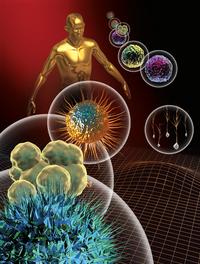

L’EFS est un acteur vital pour le système de santé français, aussi vital, pourrait-on dire, que le sang l’est pour l’organisme. Acteur public, placé sous la tutelle du Ministère de la santé et de la prévention, il est garant de l’autosuffisance du pays en produits sanguins labiles. Mais pas seulement ! Avec 10 000 professionnels répartis dans toute la métropole et les t